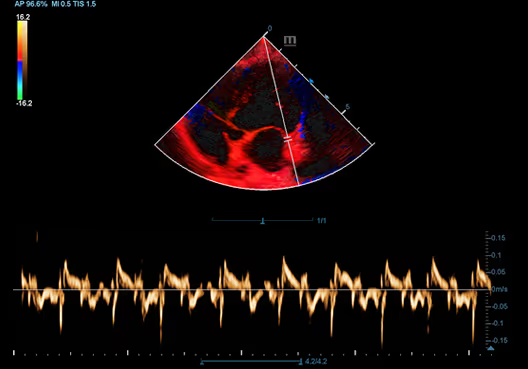

Köpek Kalbinin TDI QA'sı

Köpek Kalbinin TDI QA'sı

Köpek Kalbinin TVD'si

Köpek Kalbinin TVD'si

Köpek Kalbinin TVD'si

Köpek Kalbinin TVD'si